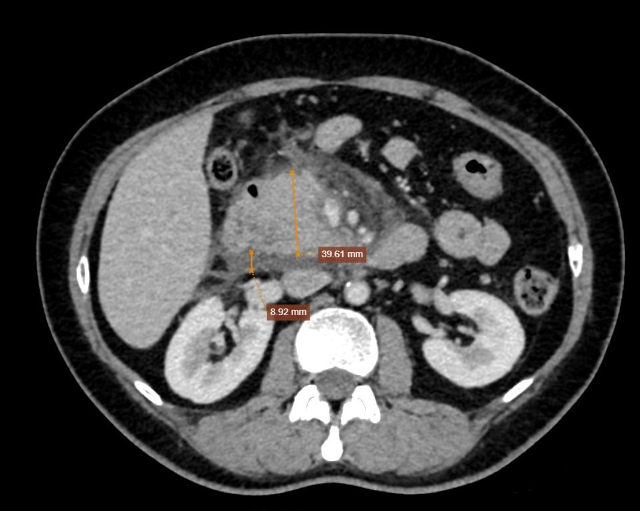

Hình ảnh đầu tụy tăng kích thước, đường kính xấp xỉ 40mm được ghi nhận trên phim chụp CT |

Chụp CT ổ bụng có đầu tụy tăng kích thước, đường kính xấp xỉ 40mm. Bờ tụy đều, xung quanh tụ dịch dày 8mm, dịch lan ra khoang cạnh thận phải, gốc mạc treo dày 5mm. Hình ảnh viêm tuỵ cấp (Balthazar D).

Dựa vào thăm khám, xét nghiệm, bệnh nhân có chẩn đoán xác định bị viêm tụy cấp Balthazar D do tăng Triglycerid - Stent mạch vành - Rối loạn chuyển hóa lipid máu.